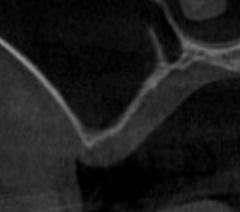

初診時(デンタル) 初診時(CT)

根管充填が不十分で、すき間もあり不良である